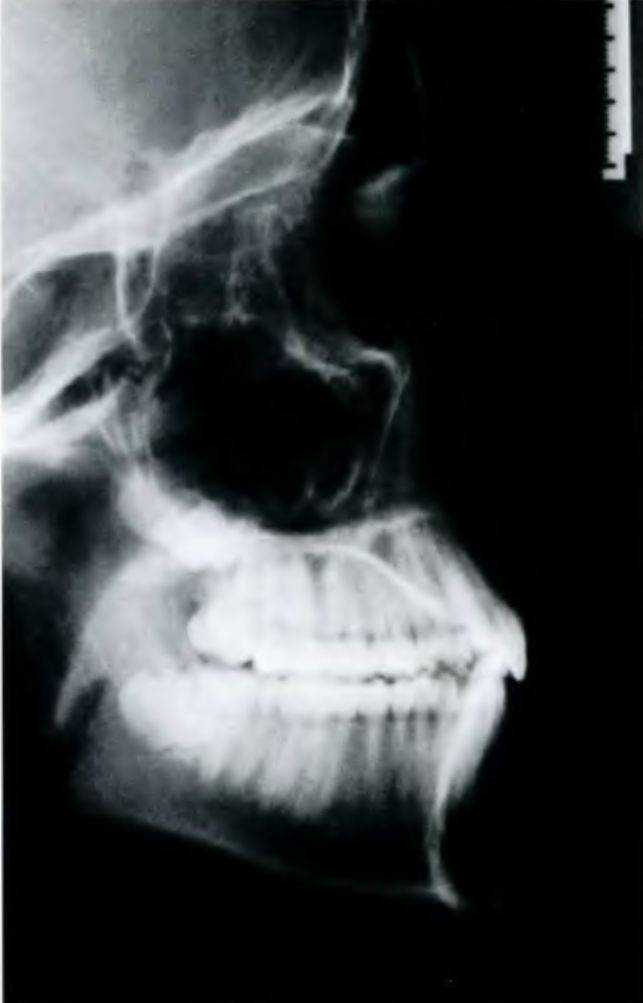

Рис. 6-9Ь. Боковая цефалограмма

Значение обеих эстетических линий можно продемонстрировать на практическом примере. Ортодонтическое лечение молодого человека было успешно завершено 10 лет назад (рис. 6-9а и 6-9Ь). К лицу пациента приложили линейку и оценили его профиль относительно эстетических линий Рикеттса (рис. 6-9с) и Холдавея (рис. 6-9d). Анализ контура показал, что расстояние между верхней губой и каж-

дой из эстетических линий было на 1 мм больше, чем необходимо. Изучение моделей (рис. 6-9е) показало, что верхние резцы слишком сильно наклонены вовнутрь, что и привело к ретрузии верхней губы.